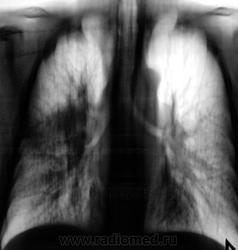

Вот и контроль после лечения подоспел...

Динамики нет... К онкологам пойдет?

А клиника после лечения как? Визуально-то - не "айс". Мягко говоря - без динамики.

К онкологам.

Жалоб нет, температуры нет, только кашель с мокротой. Мокрота со слов пациента и жены его светлая, без примесей.

А куда он денеться если надо..., немного покобенится конечно...